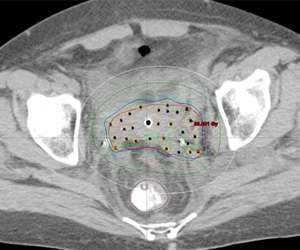

Below is an actual example of the CAPRI applicator (a 13 channel applicator) and the distribution of radiation dose that was delivered around the vaginal apex (right image axial and left image sagittal). Below to the right is a 3D depiction of the anatomy and distribution of the radiation dose (bladder in yellow, rectum in brown, applicator in purple, radiation dose in red):

CAPRI applicator

3D depiction

3D depiction of the anatomy and distribution of radiation dose.